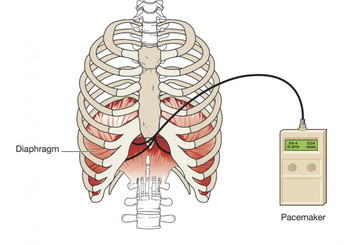

Speaking Valve and Diaphragm Pacing: Changing Lives

The Role of the Passy Muir® Valve in the Pulmonary Management of the Patient with a Spinal Cord Injury